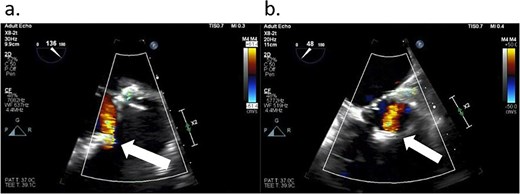

After the aortic cross-clamp was removed, transesophageal echocardiogram (TEE) demonstrated what was suspected to be a mild-to-moderate paravalvular leak along the non/right coronary cusp commissure. The jet appeared highly eccentric and perpendicular to the flow of the left ventricular outflow tract (Fig. 1). Given the size of the leak, it was decided to rearrest the heart. After reopening the aortotomy and assessing the bioprosthesis, no valve defects were seen. But given the suspected friable and thin annular tissue, the base of the aorta was further reapproximated and reinforced to the external sewing ring at the right/noncoronary commissure with multiple prolene, pledgeted sutures. After the second cross-clamp was removed, TEE demonstrated a larger, now broad-based, moderate or greater regurgitant leak at the non/right commissure, and, in addition, the presence of a new mild leak along the left/right commissure (Fig. 2). At this point, a transprosthetic leak was suspected with potential malfunction of the valve. The heart was rearrested for a third time, and the bioprosthetic valve was reexamined and annulus probed. The valve was explanted without any annular pathology being evident, and examination of the valve on the back table demonstrated a torn area of cloth along the right/non and left/right commissures of the cuff at the level of the stent posts, suspected to be the site of the leaks (Fig. 3). A new same-sized 27 mm Inspiris Resilia valve was chosen, and the valve was placed on to the annulus in a supra-annular fashion with multiple ventricularly based 2-0 Ethibond EXCEL pledgeted mattress sutures, and secured with the COR-KNOT device.

TEE demonstrating two leaks from the Inspiris Resilia valve after the second aortic cross-clamp was removed. A larger now broad-based, moderate or greater regurgitant leak at the non/right commissure (long arrow), and a new mild leak along the left/right commissure (short arrow).